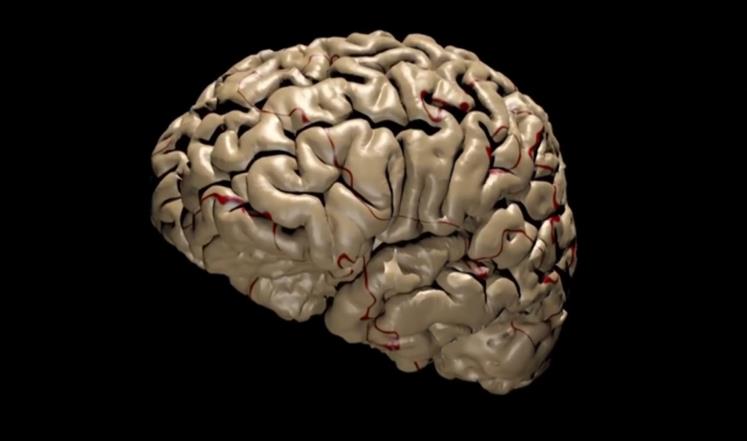

حذرت دراسة فنلندية حديثة من تناول الخمور لتأثيرها على تطور بنية الدماغ البشري خلال فترة المراهقة والشباب.

وأظهرت الدراسة أن شرب الخمر يؤثر على بنية الدماغ عبر تقليص حجم المناطق الرمادية فيه، كما يؤثر على تشكيل “القشرة الحزامية الأمامية”.